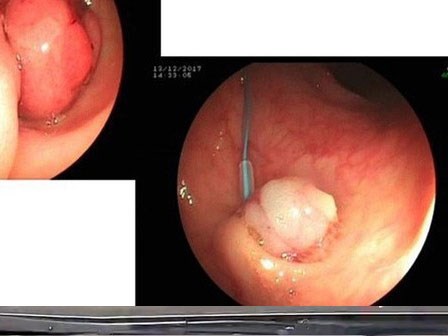

Bệnh ung thư dạ dày nguy hiểm như thế nào mà ai ai cũng sợ?

Ung thư dạ dày là căn bệnh ung thư thường gặp thứ 3 trong các bệnh ung thư ở đường tiêu hóa và là bệnh có độ ác tính rất cao.